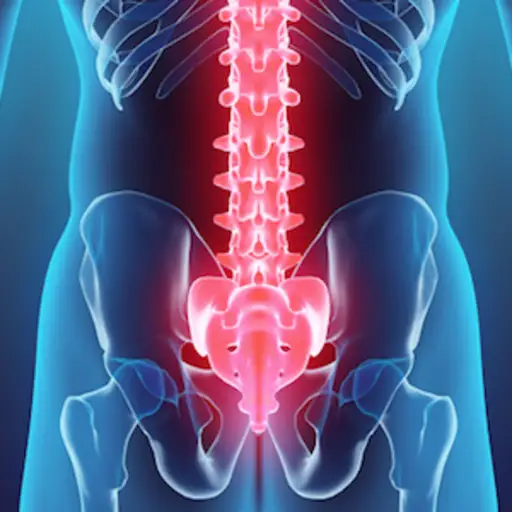

在免疫介导的炎症疾病中,免疫系统发生故障并攻击健康组织。主要影响脊柱,导致椎骨和脊髓的炎症,例如位于脊柱连接到骨盆中的骶髂(Si)关节。由于也可以影响体内的其他关节,以及眼睛和内脏。

通常在年龄17和45岁虽然它也可能发生在其他年龄。第一个症状通常从骶髂关节开始。您可能会感到较低的背部疼痛,并且在早晨或在一段时间不活动后疼痛和僵硬。其他症状包括身体其他部位的疼痛和僵硬,尤其是Achilles肌腱,臀部外侧,沿着胸骨。

与许多其他类型的炎症关节炎一样,因为可能导致严重,慢性疼痛在身体的受影响的区域。在非常先进的情况下,疾病会导致新的骨形成,基本上融合脊柱。有时这种融合导致前抚养姿势脊柱疮。

最常见的并发症是脊柱的融合。它也可能导致肋骨中的融合,可能会影响肺功能。其他潜在的并发症包括葡萄膜炎(眼睛的炎症,引起疼痛,视力模糊和对光的敏感),虹膜(和影响眼睛瞳孔周围的彩色环)的炎症,脊柱中的压缩骨折。炎症也可以影响主动脉,扩大它并影响心脏功能。